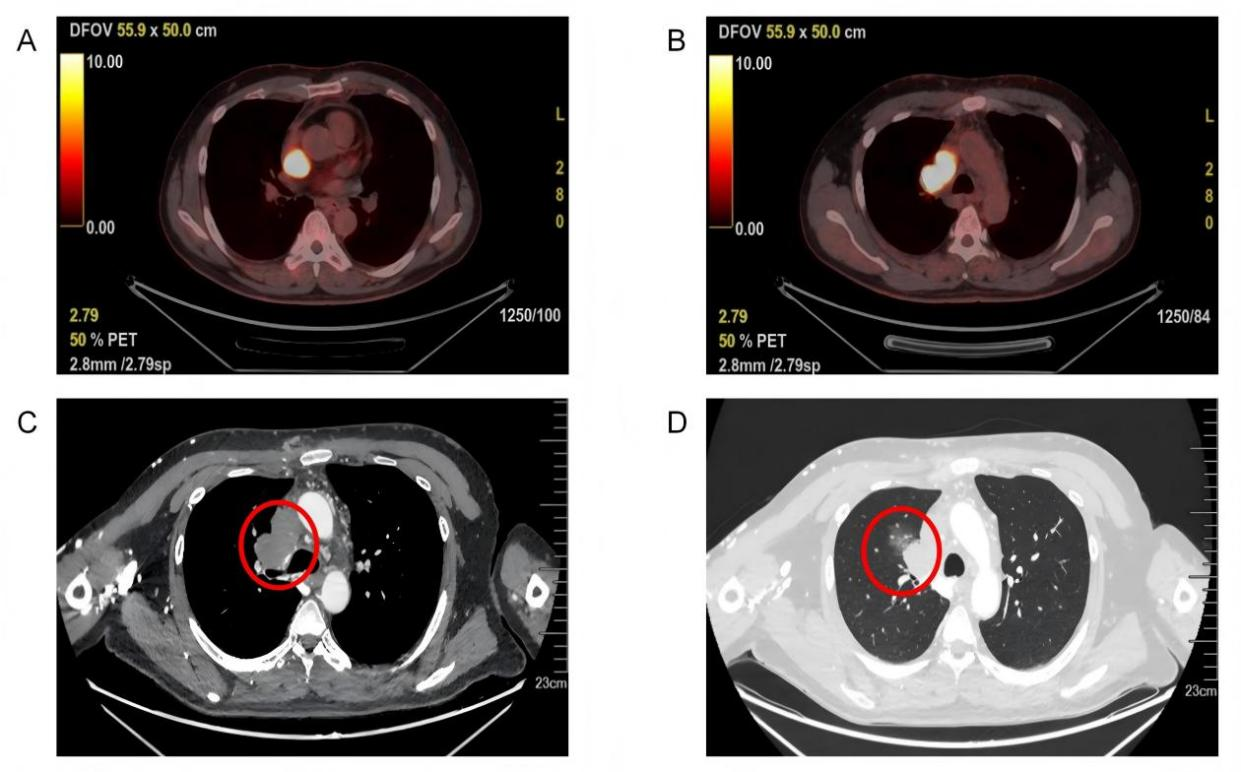

患者检查影像图:A:肿瘤侵占右心房;B:肿瘤堵塞上腔静脉;C:肿瘤压迫右主支气管;D肿瘤侵犯右侧肺门

据介绍,去年年底,李先生发现自己的脸越来越肿,脖子上的血管也越来越明显,整个人发胀、难受,却说不清问题究竟出在哪里。到医院进一步检查后,结果让人吃了一惊:胸腔内布满肿瘤,一路蔓延侵入心脏,堵住重要血液通道,还累及右侧肺部。由于血液回流受阻,他才出现了头面部肿胀、颈部血管鼓起等一系列症状,病情随时可能进一步加重。